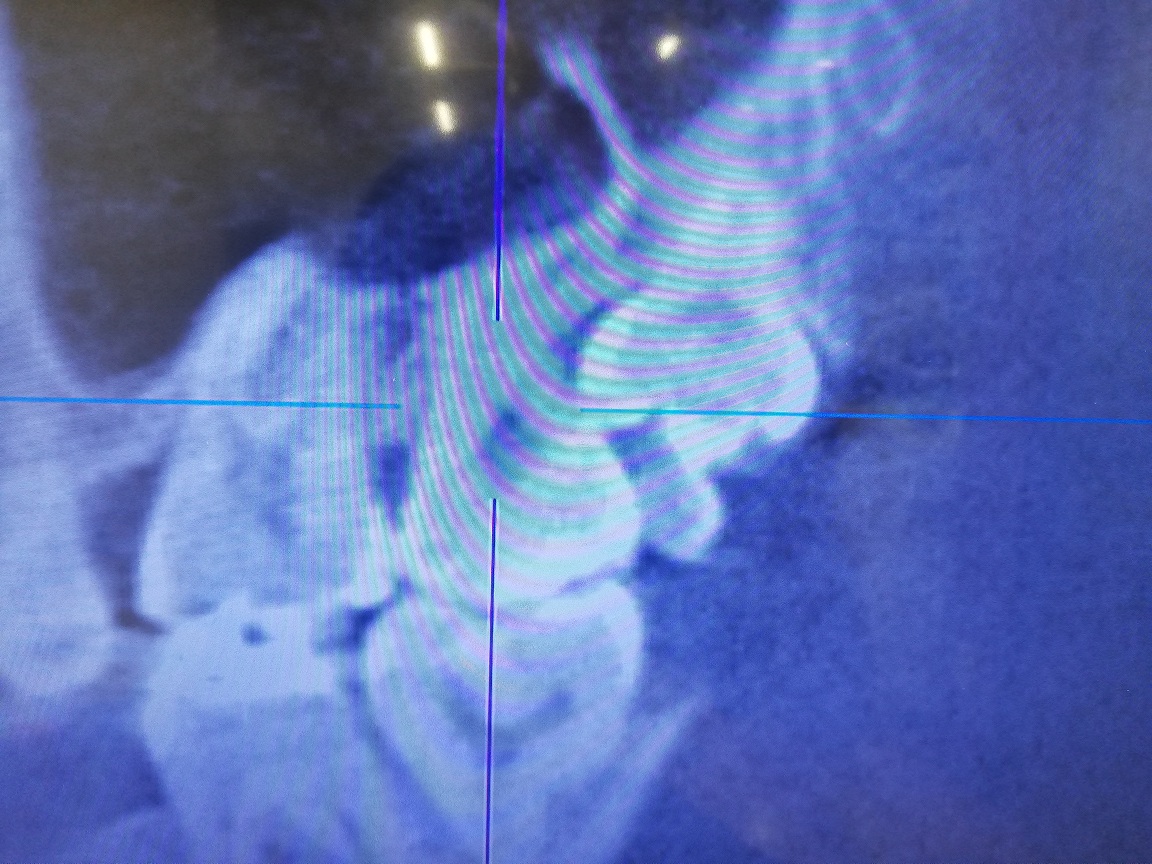

右上の親知らずについて抜いてもらおうと思いCTを撮影してもらったところ、親知らずが隣の歯を支えている状況であり、親知らずを抜くと隣の歯(7番)が揺れる可能性があるとのことでした。

抜歯のメリットは、親知らずの隣の歯を専用のブラシで清掃し管理できるようになることで、デメリットは、親知らずの隣の歯(7番)の寿命を親知らず抜歯によって、かえって縮めてしまう可能性があるとのことでした。

主治医の先生は、通常なら親知らず抜歯を勧める状況だが、わたしの場合は、通常の人よりも副鼻腔が大きく、親知らずの隣の歯(7番)の歯根が歯槽骨に埋まってる長さが少ないために、親知らず抜歯によって7番が揺れるようになる可能性があるとのことでした。さらに、親知らずが7番を支えているような状況だそうで、噛める力が弱くなる可能性もあるとのことでした。

添付の画像は、問題の親知らずのレントゲン写真とCT画像になります。

画像1右上親知らず.jpg 画像2右上親知らずCT.jpg

普段見かけないものが7番は8番の間にあるように思いますがいかがですか?

CTは合わせ方によってほぼほぼ正確な歯根の長さを確認できる場合とそうでない場合があると思います。

根管のほぼ中央に歯髄がありますので根管がきちんと写っていると長さを測りやすいと思います。

このようなケースの場合ごく稀に7番の遠心側が外部吸収していることがあります。その場合には7番を抜歯して8番を矯正治療で7番の位置に移動させられる矯正専門医はたくさんいらっしゃると思います。